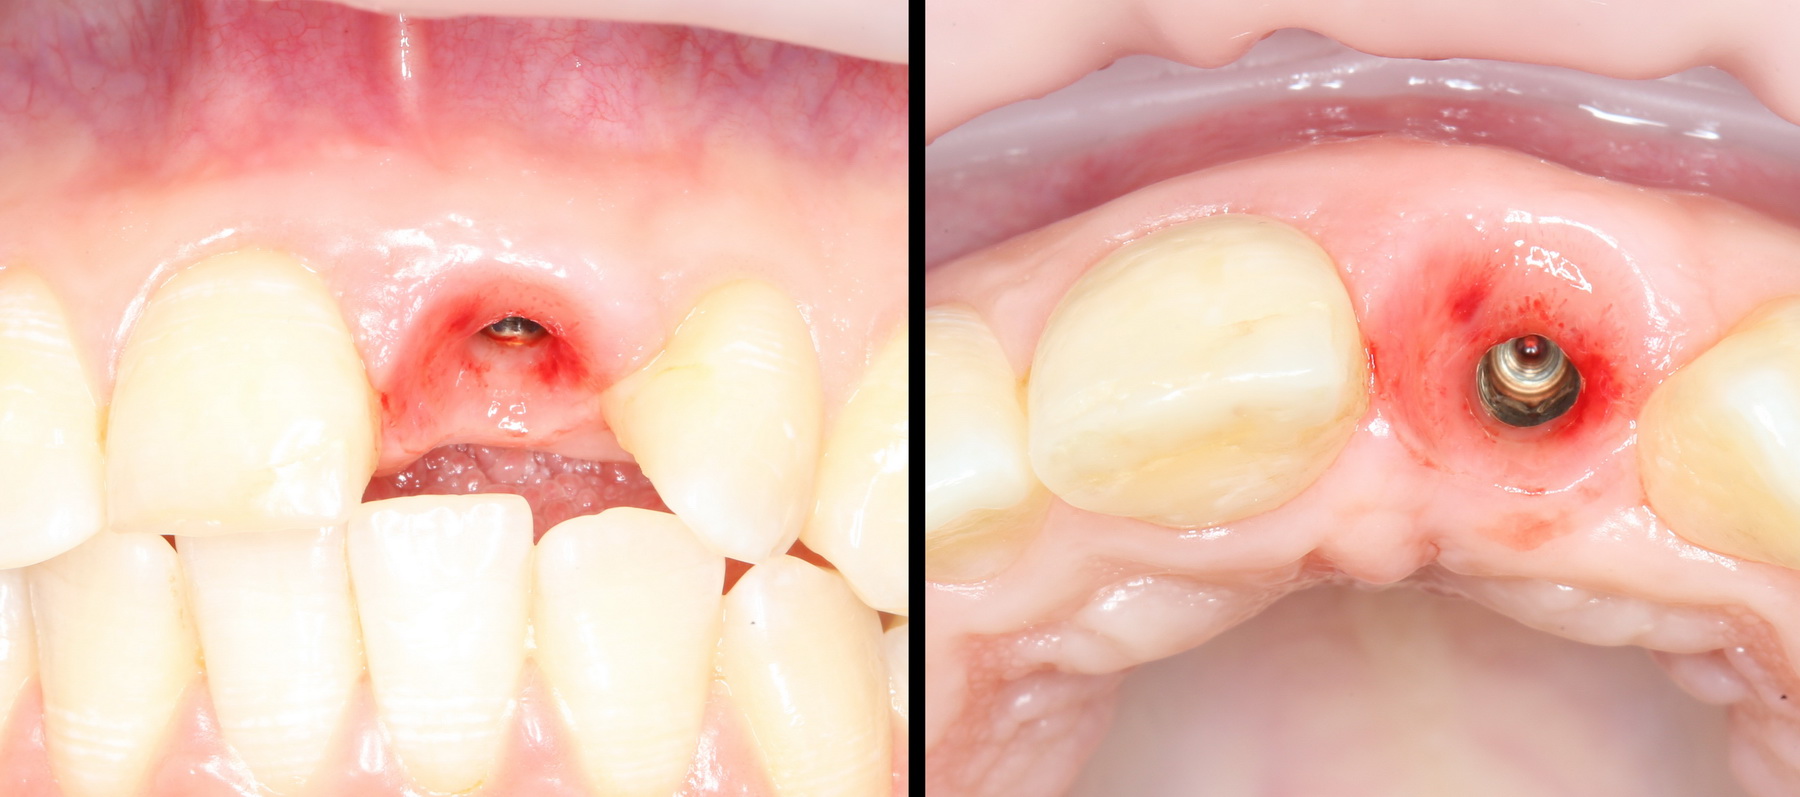

Ответственный момент. Делаем разрез и открываем имплант:

Как видите, вестибулярная стека импланта находится в новообразованной костной ткани. А это значит, что наша остеопластика удалась. Хотя, это еще нельзя назвать результатом нашей операции.

Ставим формирователь десны. Затем, Давид окончательно формирует десну с помощью временной коронки. После его формирования слизистая выглядит примерно так: